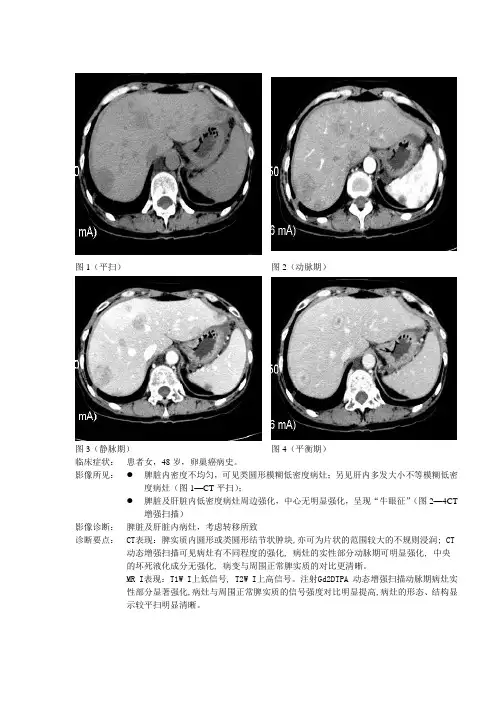

图1(平扫)图2(动脉期)

图3(静脉期)图4(平衡期)

临床症状:患者女,48岁,卵巢癌病史。

影像所见:●脾脏内密度不均匀,可见类圆形模糊低密度病灶;另见肝内多发大小不等模糊低密度病灶(图1—CT平扫);

●脾脏及肝脏内低密度病灶周边强化,中心无明显强化,呈现“牛眼征”(图2—4CT

增强扫描)

影像诊断:脾脏及肝脏内病灶,考虑转移所致

诊断要点:CT表现:脾实质内圆形或类圆形结节状肿块,亦可为片状的范围较大的不规则浸润; CT 动态增强扫描可见病灶有不同程度的强化, 病灶的实性部分动脉期可明显强化, 中央

的坏死液化成分无强化, 病变与周围正常脾实质的对比更清晰。

MR I表现:T1W I上低信号, T2W I上高信号。

注射Gd2DTPA 动态增强扫描动脉期病灶实

性部分显著强化,病灶与周围正常脾实质的信号强度对比明显提高,病灶的形态、结构显

示较平扫明显清晰。